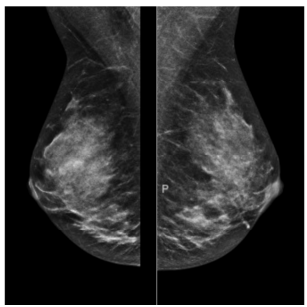

Considere as imagens da mamografia abaixo.

É possível afirmar que são imagens na posição